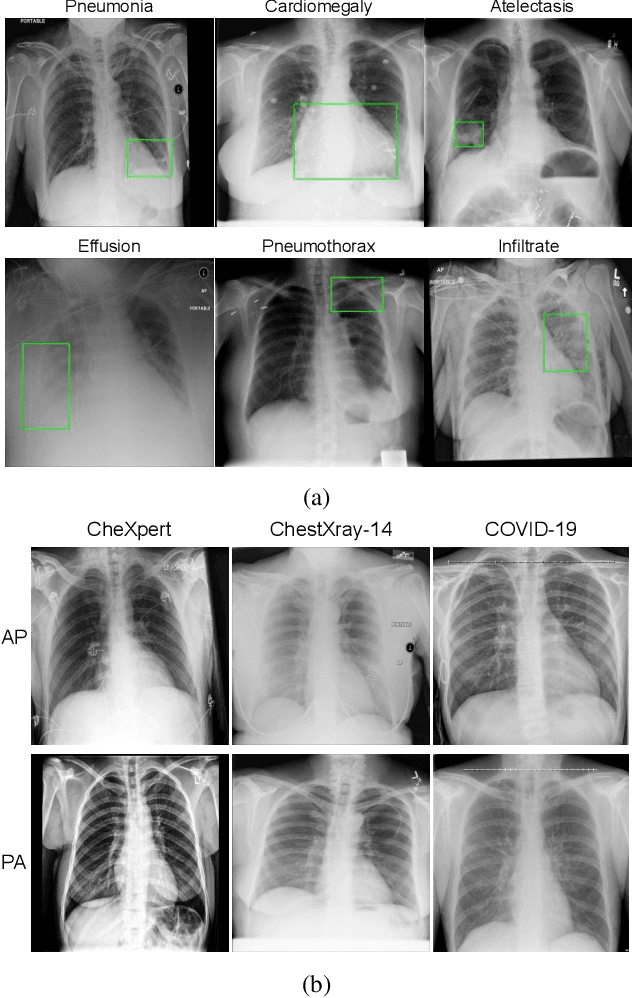

Abstract:With increasing number of COVID-19 cases globally, all the countries are ramping up the testing numbers. While the RT-PCR kits are available in sufficient quantity in several countries, others are facing challenges with limited availability of testing kits and processing centers in remote areas. This has motivated researchers to find alternate methods of testing which are reliable, easily accessible and faster. Chest X-Ray is one of the modalities that is gaining acceptance as a screening modality. Towards this direction, the paper has two primary contributions. Firstly, we present the COVID-19 Multi-Task Network which is an automated end-to-end network for COVID-19 screening. The proposed network not only predicts whether the CXR has COVID-19 features present or not, it also performs semantic segmentation of the regions of interest to make the model explainable. Secondly, with the help of medical professionals, we manually annotate the lung regions of 9000 frontal chest radiographs taken from ChestXray-14, CheXpert and a consolidated COVID-19 dataset. Further, 200 chest radiographs pertaining to COVID-19 patients are also annotated for semantic segmentation. This database will be released to the research community.